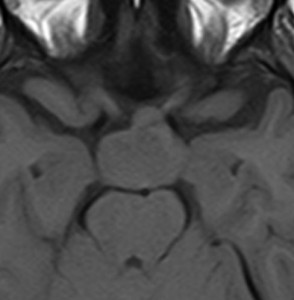

典型的な神経腸嚢胞 neurenteric cyst

左のT2強調画像で等信号,中のT2*で高信号,右はCISS画像です。

T1強調画像では,のう胞周囲の高信号の部分は半固体で,中心部の高信号はドロドロの粘液でした。基本的にガドリニウム増強はされません。まれに薄い膜状に一部が増強されることがあります。

境界明瞭は袋状の腫瘍です。椎骨動脈や脳底動脈を包み込むようにふくらんでいます。